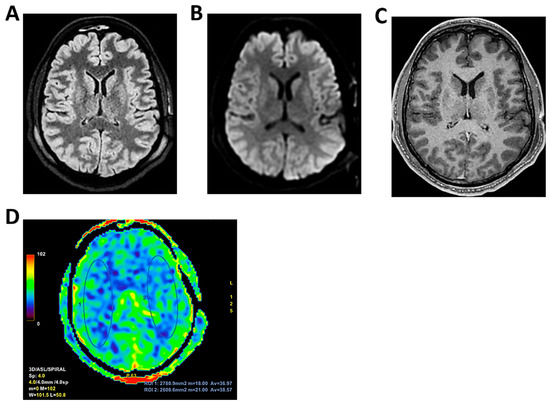

Background: Meningoencephalitis is a complex inflammatory condition of the CNS that can result in significant morbidity and mortality in critically ill adults. Accurate and timely neuromonitoring is essential for guiding management and improving outcomes. This study aimed to descriptively evaluate the prognostic value of early TCCD monitoring, particularly the pulsatility index, and its integration with conventional and perfusion MRI in patients with meningoencephalitis. Methods: We present an observational, retrospective, cohort study involving ten adult patients (median age 56 years, IQR 45.5–68.5; mean 55.9, range 35–76) with neurological syndromes caused by suspected or confirmed infectious meningoencephalitis. Etiologies included bacterial meningitis/meningoencephalitis (50%), viral meningoencephalitis (10%), neurotoxoplasmosis (10%), progressive multifocal leukoencephalopathy (10%), and undetermined origin (20%). Patients underwent TCCD and MRI within 24 h. In five cases, standard MRI sequences were acquired, while in the remaining five, perfusion imaging was performed using Arterial Spin Labelling (ASL). A favorable outcome was defined as survival with neurological recovery (Glasgow Outcome Scale > 5) at ICU discharge. Results: TCCD-derived PI provided valuable information on cerebral hemodynamics. PI values ≤ 1.25 were associated with favorable clinical outcomes and symmetrical MRI findings. Conversely, PI > 1.25 correlated with poor prognosis and often preceded MRI-detectable structural damage. When combined with ASL, PI mirrored the detected perfusion asymmetries and was associated with poor prognosis in fatal cases. Conclusions: Bedside TCCD can offer real-time assessment of cerebrovascular dynamics and, when integrated with conventional and ASL MRI, could enhance the understanding of pathophysiological processes in meningoencephalitis, supporting timely and informed decisions in neurocritical care.